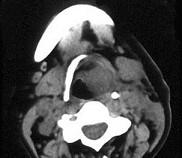

问题 女、54岁,鼻咽部异物感约三个月,PE:左侧声带固定,可见肿物,CT如图所示,应诊断为()

选项 A.喉部乳头状瘤 B.喉癌 C.喉部血管瘤 D.慢性增生性喉炎 E.增生型喉结核

答案 B